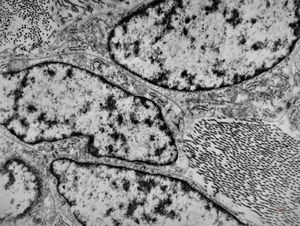

M,50y. | Pneumocystis carinii - lung